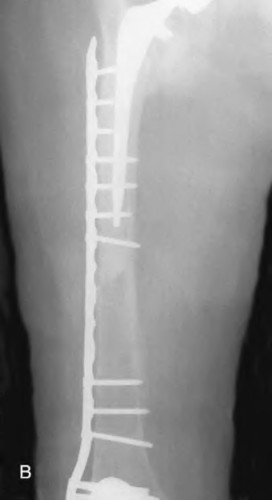

A 72-year-old female presents with acute thigh pain and an inability to bear weight after a minor fall, 10 years post-THA. Radiographs demonstrate a fracture around the tip of the well-fixed femoral stem, extending into the diaphysis. The bone stock proximally remains intact. Which principle must be strictly adhered to during the surgical fixation of this fracture?

Explanation